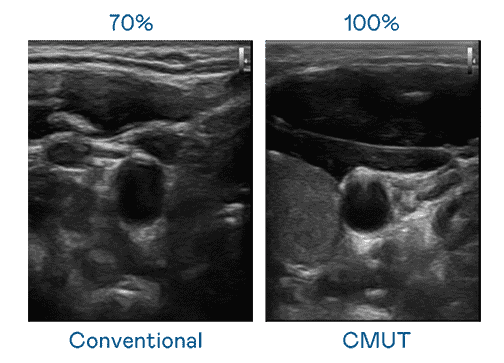

CMUT 技术是一种用电容式微机电元件来产生超音波讯号的技术。。。与传统 PZT 压电式技术相比,,,,CMUT 频宽增加 30%,,,更宽频的超音波讯号让影像解析度大幅提升,,,是实现高影像品质医疗超音波扫描、、、、促进精准医疗发展的关键技术。。

超音波影像的解析度高低,,,,首先取决于探头能发出的讯号频宽。。。JDB电子 CMUT 可提供高清晰的超音波讯号,,,提供高频宽、、、、高灵敏度、、影像纹理细节更高的超音波影像,,协助医护人员缩短影像判读时间及利用精准的医疗影像进行诊断。。。。